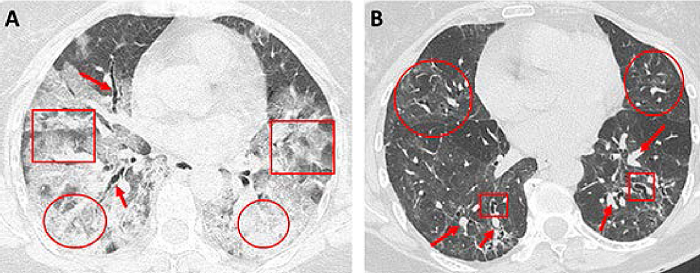

Por otro lado, las lesiones residuales o secuelas pulmonares en pacientes pos-COVID-19 han sido un tema de gran interés. En un estudio de 149 pacientes dados de alta luego de padecer COVID-19, se observó resolución completa de las lesiones pulmonares en las TACAR de 53 % de los pacientes. Sin embargo, en esta misma serie se reportó que hasta 40 % mostraba anomalías pulmonares residuales después de tres semanas del alta médica. La TACAR es útil para evaluar lesiones pulmonares que persisten despúes del cuadro de COVID-19, por lo cual es señalada como el examen imagenológico de elección en estos casos.32

Zhao et al. señalan que las secuelas pulmonares más frecuentes en las TACAR de pacientes pos-COVID-19 a los tres meses de seguimiento son:15

Engrosamiento intersticial.

Infiltrados en vidrio esmerilado.

Patrón en empedrado (crazy paving).

Otros hallazgos tomográficos incluyen bronquiectasias de tracción, disminución del volumen pulmonar y bandas fibróticas.32 Afortunadamente, los reportes de lesiones más severa como las imágenes en panalización (hallazgo tomográfico ugestivo de fibrosis pulmonar) han sido excepcionales.50,51

La evidencia actual sugiere que los pacientes graves que desarrollaron SDRA experimentan una recuperación más lenta de las lesiones. Esto a su vez se traduce en la posterior aparición de secuelas pulmonares en la TACAR.33 Se estima que la edad puede desempeñar un papel importante en la recuperación de las lesiones, ya que los adultos mayores tienen tasas más altas de progresión hacia fibrosis pulmonar. Otros potenciales predictores de fibrosis pulmonar pos-COVID-19 son la severidad de la enfermedad, estancia prolongada en UCI, necesidad de ventilación mecánica, tabaquismo y alcoholismo.52 Sin embargo se necesita una mayor cantidad de estudios para definir los patrones de predicción de fibrosis pulmonar.

Siguiendo el esquema de monitoreo propuesto, es posible tener una visión oportuna de los cambios que se presentan en el seguimiento de los pacientes. Hemos reportado cómo se ve la modificación de las pruebas de función respiratoria durante los primeros seis meses de seguimiento en una paciente con neumonía grave por COVID-19.57 Claramente se puede apreciar cómo los valores van aumentando a medida que pasan los meses luego de haber iniciado tratamiento con rehabilitación pulmonar y oxigenoterapia durante las primeras semanas de convalecencia (Cuadro 5). Del mismo modo, al inicio de la enfermedad se observan imágenes de consolidación asociada a un patrón en empedrado en la TACAR (Figura 6A); en tanto que a los seis meses, en la TACAR de control es posible observar bronquiectasias de tracción, engrosamiento de septos interlobulillares y tenues infiltrados en vidrio esmerilado ( Figura 6B).